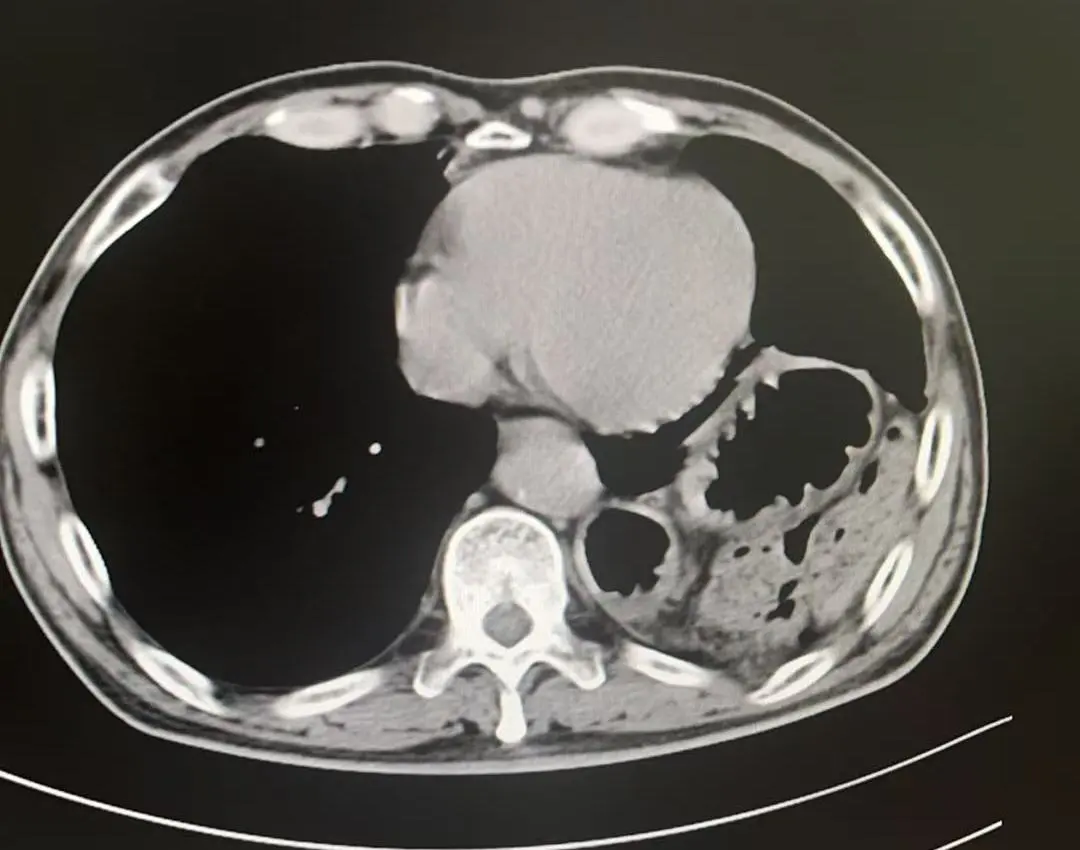

术前影像

辗转来到市二院胸外科,孙振教授在细致追问病史时,捕捉到一个关键细节:10年前,患者胸腹部曾被刀刺伤,当时仅做了外部缝合,未深入排查内部损伤。这一信息引起了孙振教授的高度警觉——很多陈旧性胸腹外伤虽表面愈合,却可能遗留膈肌破裂的隐患,并随时间推移发展为创伤性膈疝。腹部增强CT结果证实了这一判断。

膈肌是胸腔和腹腔的“分隔墙”,这道墙破了,脏器就会“跑错门”,引发连锁灾难!刘大爷的疝内容物较多、粘连严重,需尽快手术干预。

术中发现胃、结肠、小肠及脾脏疝入胸腔且与周围组织严重粘连,部分脏器难以通过微创完全复位。孙振教授果断决策,通过10厘米切口精细分离粘连,成功还纳全部脏器并牢固修补缺损,杜绝复发隐患。